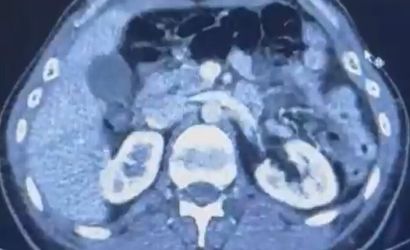

Kayseri Şehir Hastanesi'nde yapılan iç beden muayenelerinde, S.C. ve R.B.C. isimli şahısların mide kısımlarında toplam 50 adet kapsül şeklinde toplamda 554 gram uyuşturucu madde bulundu.

ŞÜPHELİLERİN MİDESİNDE KAPSÜL ŞEKLİNDE YARIM KİLO UYUŞTURUCU MADDE ELE GEÇİRİLDİ.